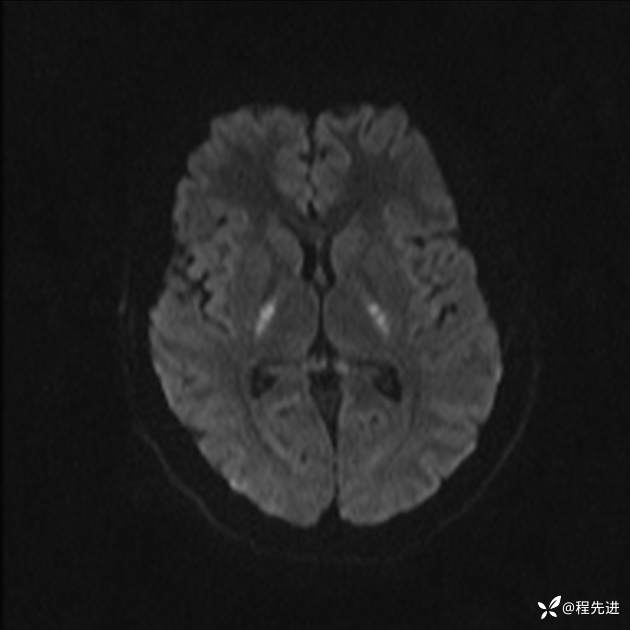

【患者信息】:女,25岁

【现病史及既往史】:言语含糊、意识状态改变1天。有下段剖宫产术10天病史。